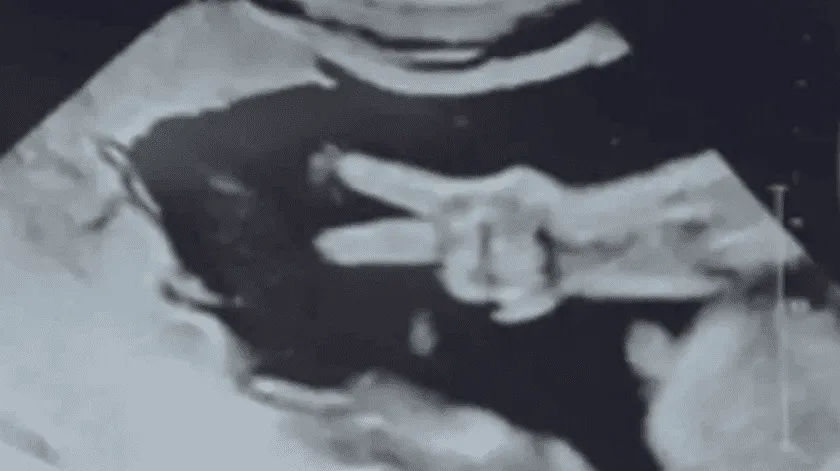

Se volvió viral en redes sociales la historia de una pareja que al acudir al ultrasonido para ver a su pequeña, el bebé los sorprendió haciendo una peculiar señal.

Fue en el noroeste de Indiana, en Estados Unidos, que la pareja Hammond se viralizó cuando compartieron al internet la foto del ultrasonido de su pequeña bebé.

Los padres acudieron de manera normal a revisión de su pequeña cuando tanto ellos como el médico quedaron sorprendió al ver que la mano de la bebé hacía